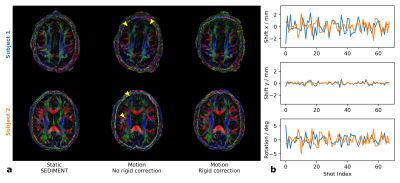

Figure 4: Colored FA maps and rigid parameters of 4-shot 15-direction DTI datasets recovered by SEDIMENT. a: Maps of two subjects acquired statically without (left column) and dynamically with voluntary in-plane motion (center and right column). b: Rigid parameters throughout multi-shot DTI experiment (shot index is a surrogate for time). The severe misalignment artifacts (arrows) are effectively mitigated by rigidly corrected SEDIMENT. Note the slight through-plane motion between the datasets for subject 2.